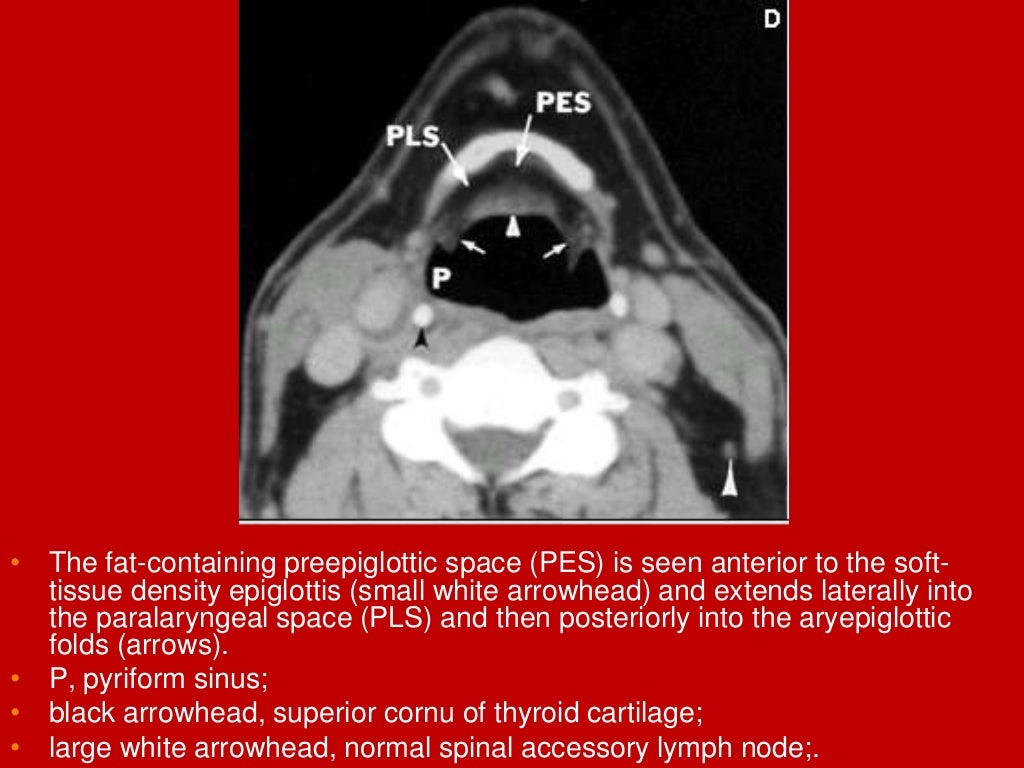

Normal larynx. (a) Axial CT scan shows the normal appearance of the Mri Anatomy Larynx Ct and mri images of the sagittal plane of larynx. Presents imaging findings in benign and malignant disease. Mri is rarely used for laryngeal imaging, but may be valuable when assessment of laryngeal cartilage invasion is of critical importance. The aim of this paper is to give a comprehensive radiological overview of larynx and hypopharynx complex anatomy, combining in vivo. Mri Anatomy Larynx.